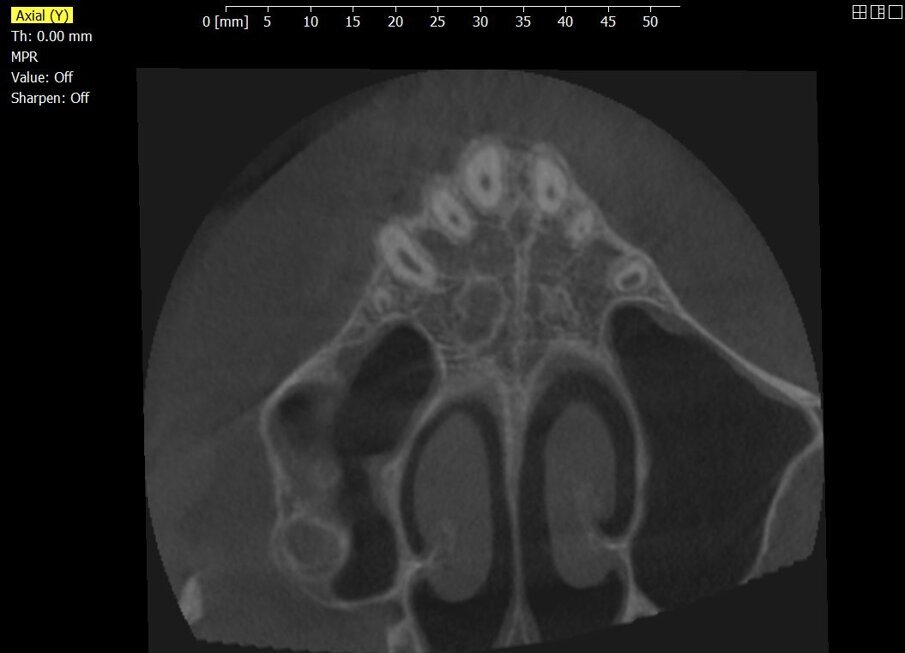

Partendo con l’acquisizione di una impronta digitale delle arcate dentarie mediante uso di scanner intraorali, o di scansione di modelli per la pianificazione del trattamento ortodontico, la metodica computer-aided design (CAD) permette la progettazione virtuale di una dima chirurgica di posizionamento per TADs basata sull’imaging della tomografia computerizzata a fascio conico (CBCT) e realizzata con computer-aided manufacturing (CAM)5, 6, 9, 10.Inoltre, tramite CBCT è possibile valutare la densità ossea e il livello di interdigitazione dei ponti ossei della sutura palatina, valutazione indispensabile per la scelta della modalità di espansione da performare.In questo case report vogliamo dimostrare come il workflow digitale abbia aiutato il clinico sia nella fase di diagnosi che nella progettazione e risoluzione della problematica ortodontica.

_Materiale e metodi Una paziente di sesso femminile di 11 anni, presenta all’esame clinico: dentizione permanente, palato di forma ogivale, discrepanza trasversale, affollamento e contrazione dell’arcata superiore, tipping vestibolare dei primi molari superiori, marcato affollamento dentale inferiore, tipping linguale degli elementi dentali postero-inferiori, proinclinazione vestibolare degli incisivi inferiori (Fig. 1). La paziente, inoltre, riferisce il menarca sei mesi prima dell’inizio della terapia. Per prima cosa è stato realizzato un setup digitale del risultato finale nell’arcata inferiore correggendo l’affollamento mediante espansione dei settori posteriori e minimizzando la proinclinazione degli incisivi. Utilizzando questo setup digitale come arcata guida, è risultata una discrepanza trasversale tra arcata inferiore e arcata superiore di circa 6 mm (Fig. 2).Richiesto l’esame CBCT, è stata valutata anche la morfologia della sutura palatina ed è risultata di tipo C secondo la classificazione di Angelieri et al11 (Fig. 3).

Fig. 3_La CBCT permette di analizzare la morfologia della sutura palatale, in questo caso identificata con uno stadio C.

I dispositivi di espansione rapida palatale (REP) in età infantile hanno un’azione ortopedica trasmessa alle strutture scheletriche attraverso i denti di ancoraggio, il che può portare a diversi effetti collaterali dentali indesiderati come fenestrazioni dell’osso buccale, riassorbimenti delle radici e recessioni gengivali anche nei bambini18–20. Questi effetti collaterali sono ridotti con l’uso della MARPE che presenta migliore stabilità ed effetti ortopedici maggiori21-24, un minore carico sul legamento parodontale dei denti a cui è ancorato, perché la forza espressa dall’attivazione dell’espansore, si scarica prevalentemente sull’osso piuttosto che sulla dentatura25, 26. È stato dimostrato che la MARPE è in grado di agire su tutta la lunghezza della sutura palatina con un movimento più parallelo in direzione antero-posteriore e l’efficacia in termini di separazione della sutura è maggiore rispetto alle meccaniche tradizionali27, 28. Comprendere la variabilità individuale nella fusione della sutura palatale è essenziale per identificare quale paziente può essere sottoposto a espansione con REP o con MARPE. La classificazione di Angelieri et al. della morfologia e della maturazione della sutura palatina si basa sull’esaminazione della CBCT, da cui scaturiscono 5 stadi (A, B, C, D, E). Lo stadio della sutura della paziente di questo case report è di tipo C, nel quale la sutura appare parzialmente interdigitata; sono presenti 2 linee parallele, frastagliate, ad alta densità e molto vicine, separate da piccoli spazi e alternate ad area a bassa densità ossea29-33. Una diagnosi iniziale di stadio C, indica una prognosi incerta per eseguire un’espansione rapida tradizionale, poiché l’inizio della fusione della porzione palatina della sutura potrebbe essere imminente11.